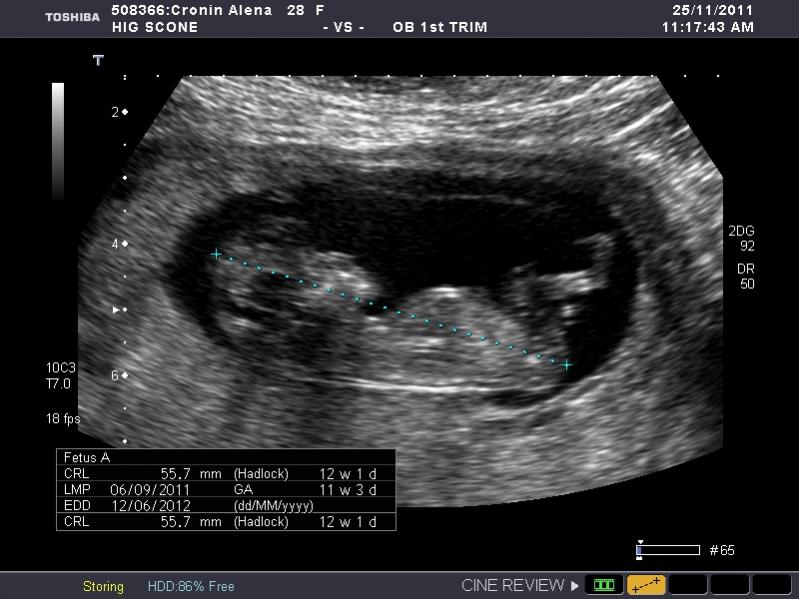

I have heaps of photos and I don't know what I am looking at so if the photo I post isn't showing anything let me know and I will try another. I am nervous as anything because I so so want a girl, but of course would still be happy with a boy. The ultrasound tech wouldn't guess.

So what is your guess.

Attachment 845Attachment 846